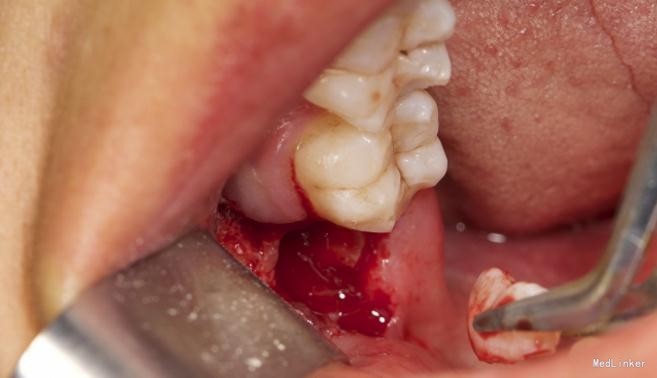

左下8水平阻生拔除

患者,男,25岁,要求拔除左下颌水平阻生牙齿,平素体质一般,无药物、食物过敏史,无高血压、心脏病等系统病史

拔除术